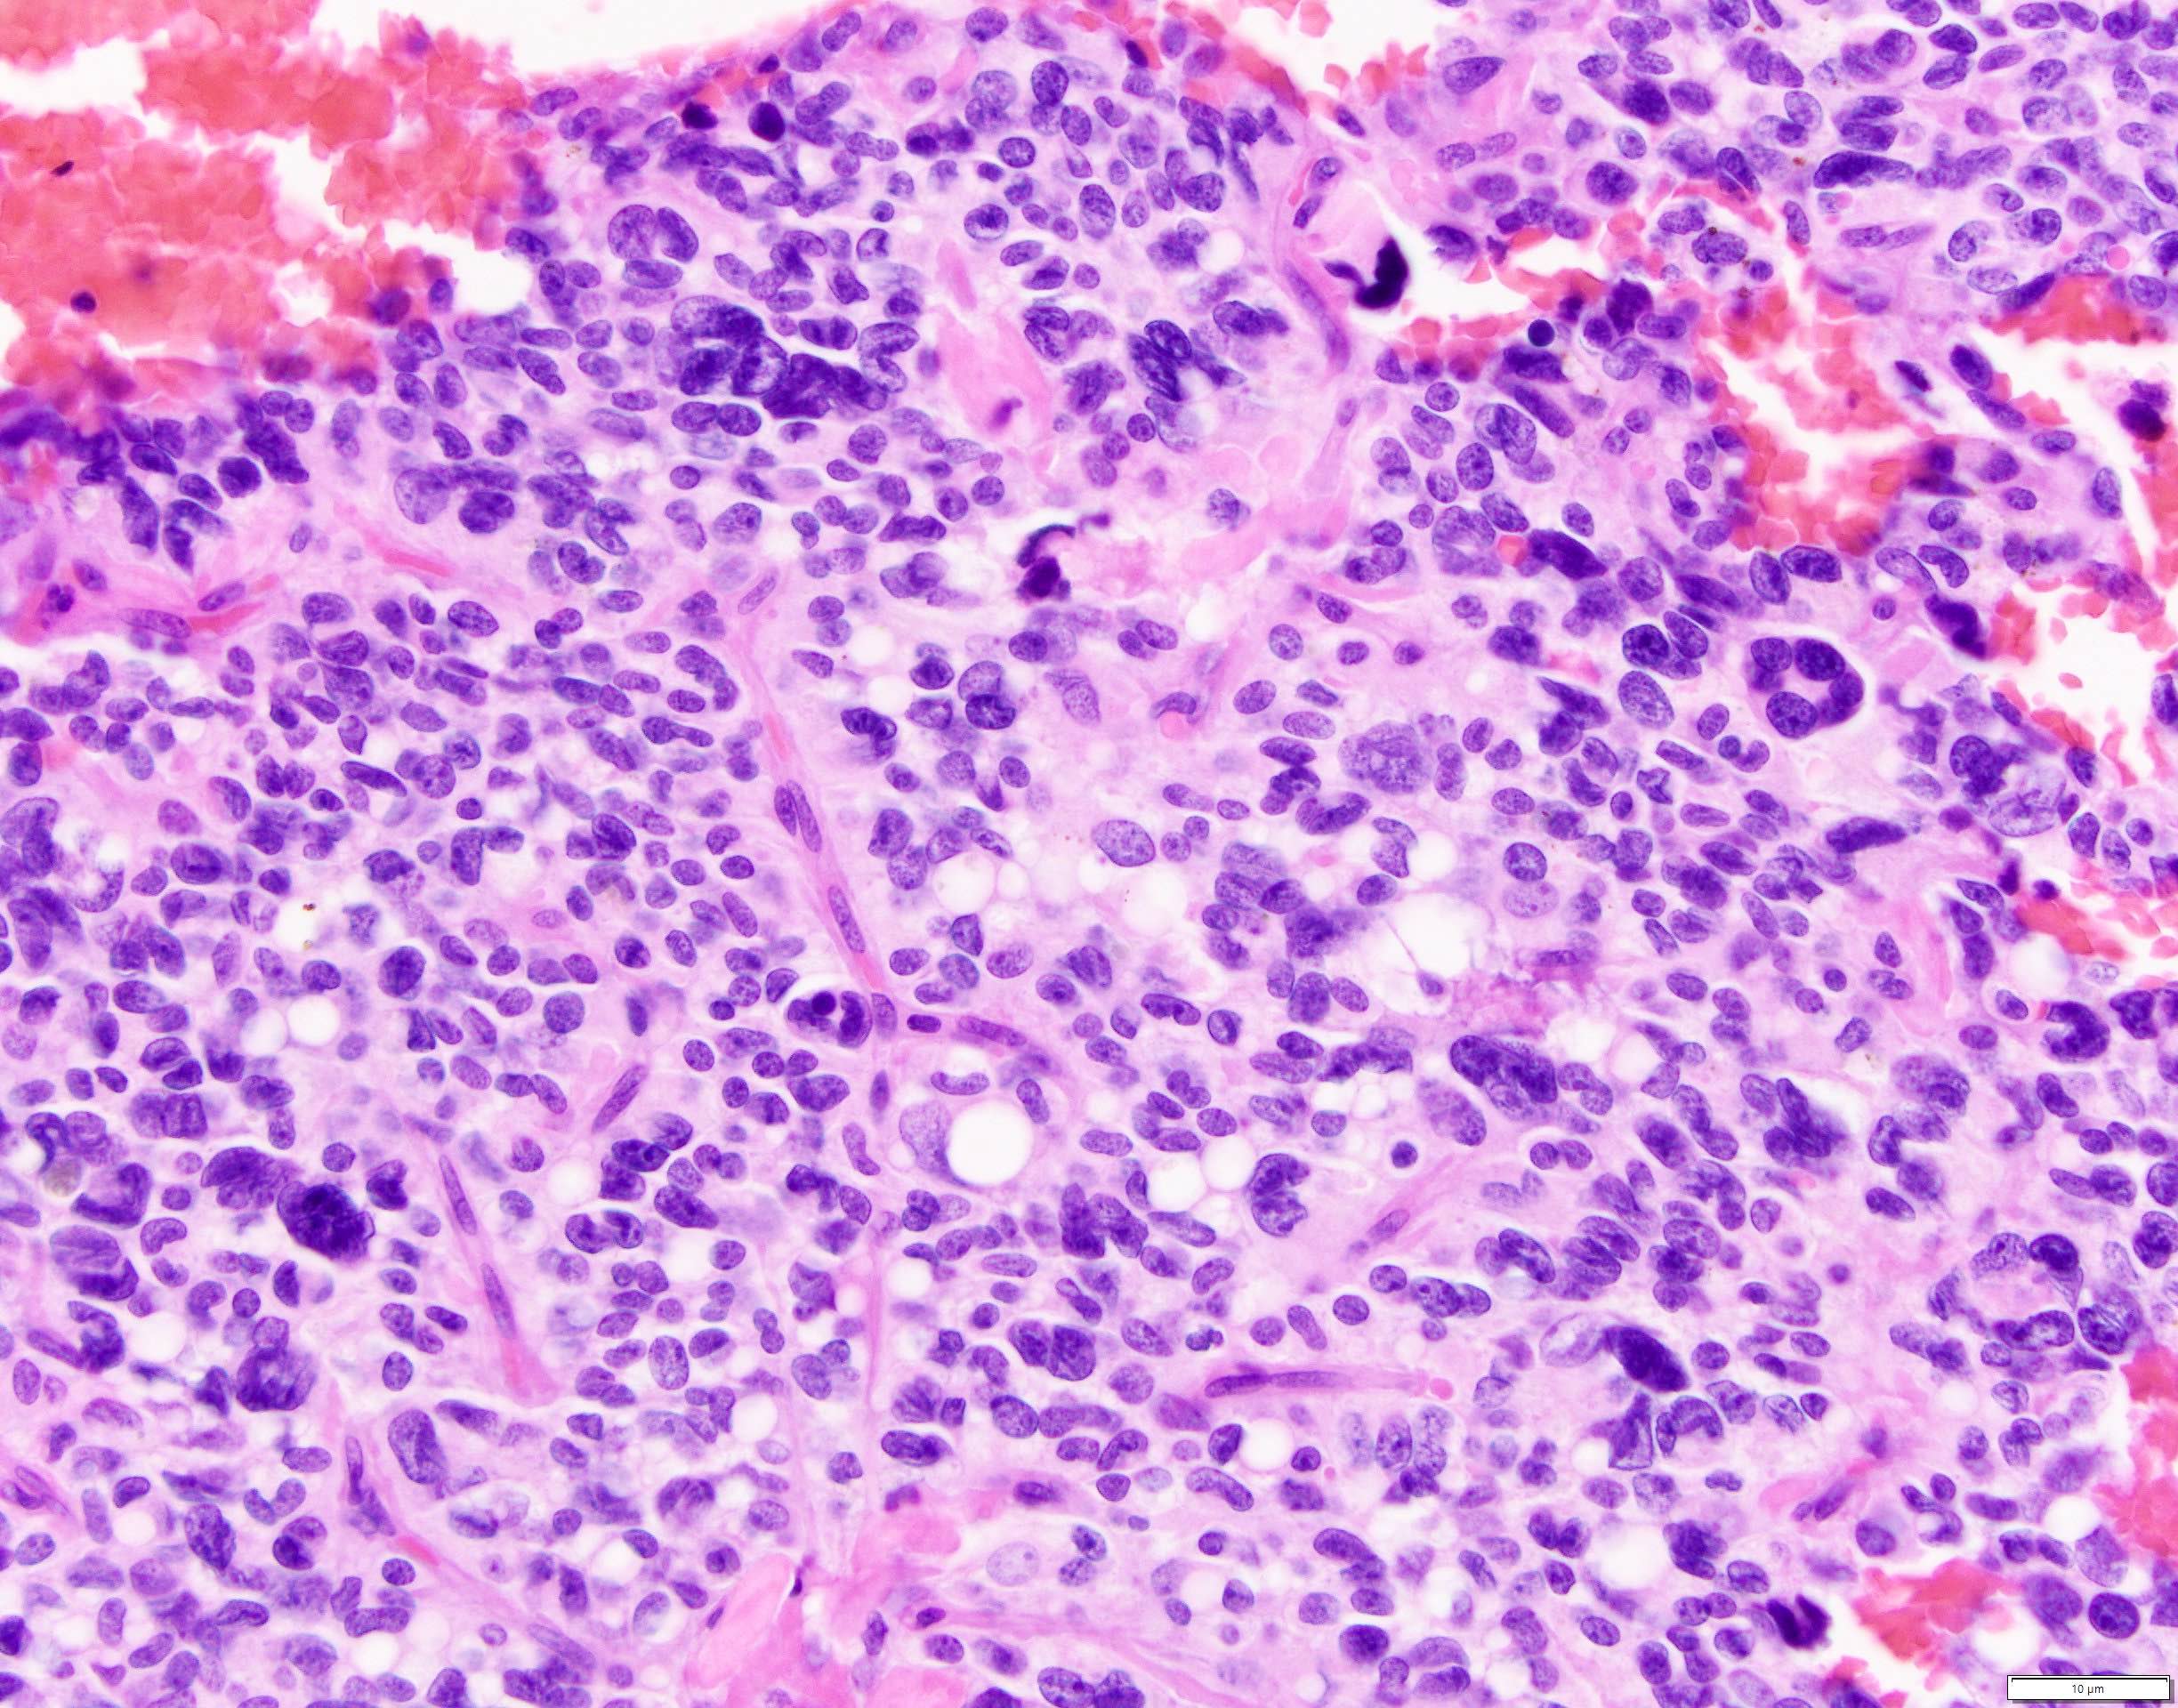

Microscopic (histologic) description

- Tumors are heterogeneous, with variable admixture of solid and pseudopapillary areas

- Solid areas are comprised of uniform cells admixed with capillary sized blood vessels

- Pseudopapillae are formed due to tumor cells getting detached from blood vessels forming fibrovascular stalks or rosette-like structures (Arch Pathol Lab Med 2020;144:829)

- Stroma usually shows various degrees of hyalinization or evidence of degeneration, such as hemorrhage, foamy macrophages, calcification and cholesterol clefts

- Tumor cells usually have a moderate amount of eosinophilic cytoplasm with intracytoplasmic hyaline globules (PAS+ and diastase resistant, positive for alpha-1-antitrypsin) and perinuclear vacuoles (Am J Surg Pathol 2011;35:981)

- Relatively uniform nuclei with finely textured chromatin, inconspicuous nucleoli and characteristic longitudinal grooves

- Variants include clear cell, oncocytic and pleomorphic

- Rare mitotic figures

- Although grossly well circumscribed, microscopic finding of infiltration to the surrounding pancreatic tissue is not uncommon

- Rare cases of highly aggressive behavior; histological features in those cases included diffuse growth pattern, extensive necrosis, significant nuclear atypia, high mitotic count (35 - 70/50 high power fields) or sarcomatoid features (Am J Surg Pathol 2005;29:512)

Microscopic (histologic) images

Contributed by Monika Vyas, M.D., Omid Savari, M.D. and Raul S. Gonzalez, M.D.